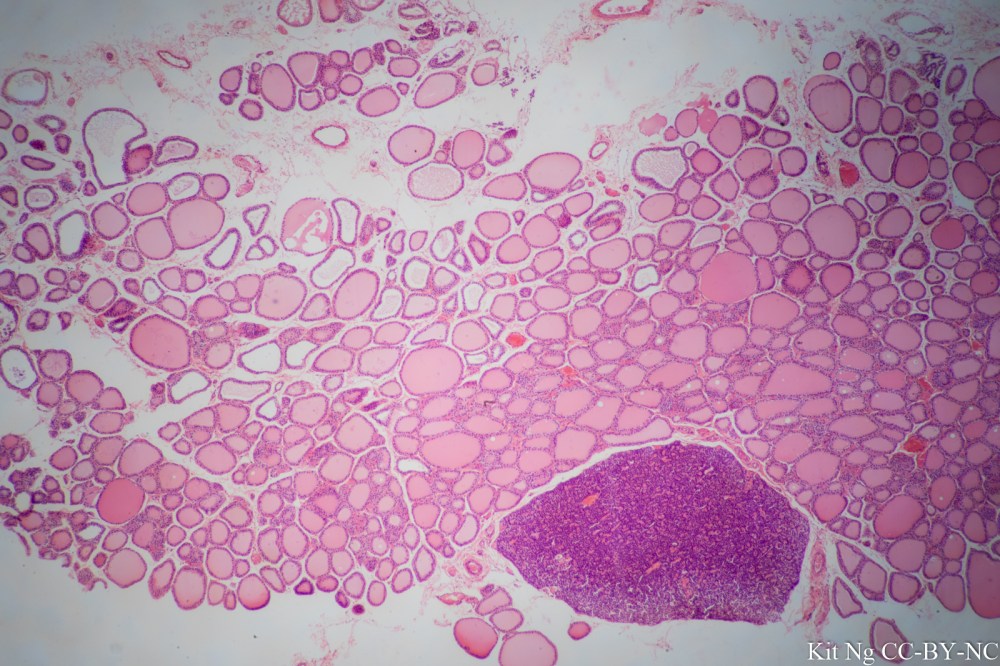

Pictures below were taken with my personal microscope, a Zeiss Standard 16 connected via a phototube to a Sony A7ii.